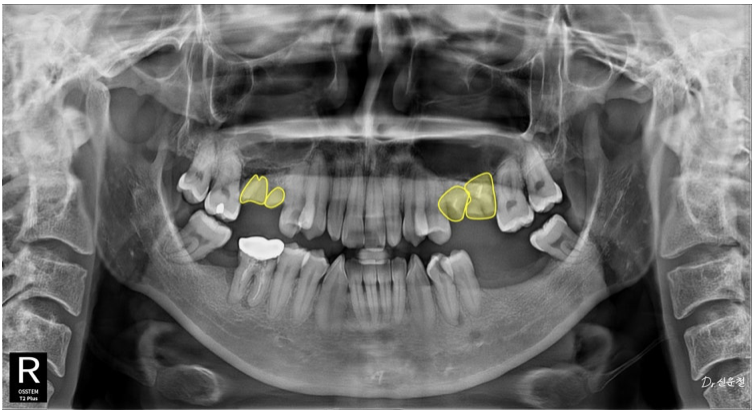

촬영일 : 250327

“사진 찍을 때 크게 못 웃겠어요.”

웃을 때는 앞니만 보이지 않습니다.

어금니까지 함께 보입니다.

앞니 배열만이 아니라 어금니 충치, 보철 색감, 잇몸 라인까지

전체적인 밸런스를 함께 봐야 합니다.